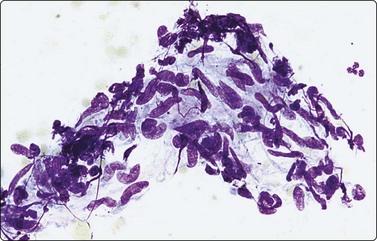

image image

Fig. 5.2 Small cell anaplastic carcinoma

Dispersed malignant cells with dense chromatin, irregular nuclear contour, nuclear molding, inconspicuous nucleoli and cytoplasm; note irregular cytoplasmic (B) and nuclear fragments in the background representing tumor necrosis (A and B) (MGG, HP).